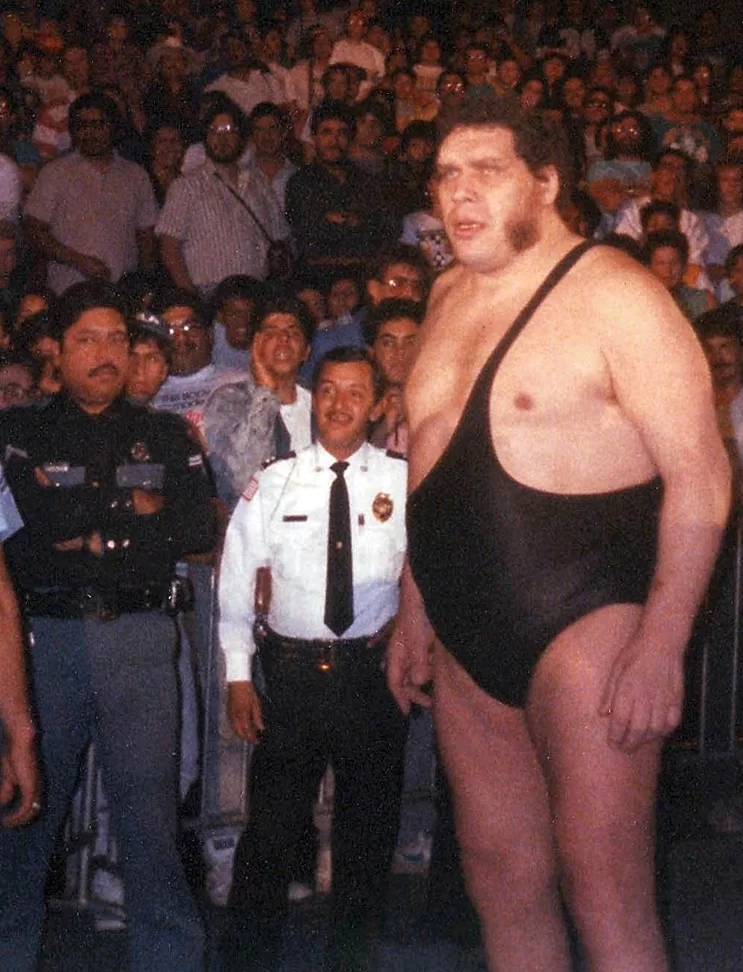

- Μια κατάσταση που ονομάζεται «ακρομεγαλία» – Αυτό συμβαίνει όταν κάποια μέρη του σώματος (ειδικά τα χέρια, τα πόδια και η γνάθος) μεγαλώνουν περισσότερο από το κανονικό (Εικόνα 2).